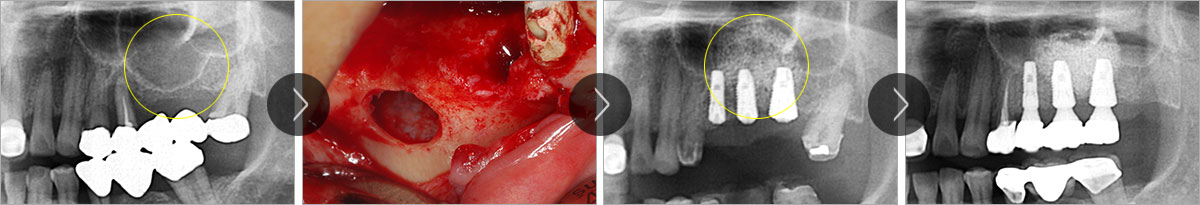

상악동이란 위턱뼈 위쪽에 코와 광대뼈 안쪽에 위치한 공기주머니 같은 부위를 말하며 두개골의 무게를 줄여 주고 숨을 쉴 때 공기 중 노페물과 먼지를 걸러주는 역할을 합니다. 상악동은 뼈가 없는 공간이기 때문에 임플란트 식립을 어렵게 하기도 하지만 사람에 따라서는 상악동이 치아 부분까지 내려오는 경우가 있습니다. 이 때 상악동을 위로 밀어올려 그 부위에 뼈이식을 함으로써 임플란트를 식립할 수 있는 충분한 공간을 확보하는 시술을 상악동 거상술이라고 합니다.

상악동 거상술의 치료과정